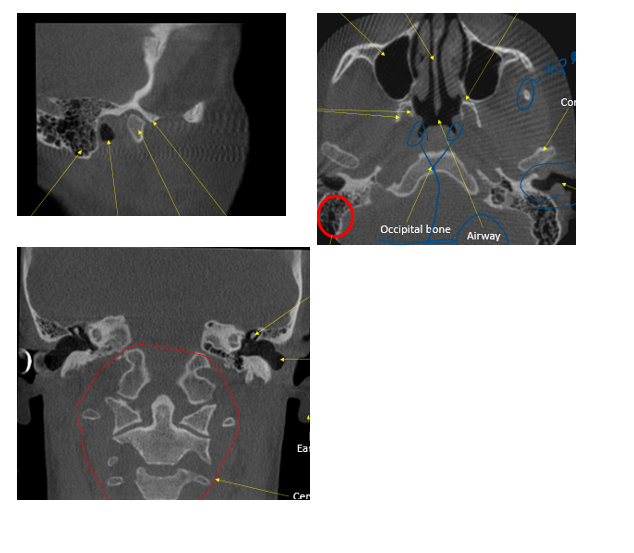

in the circle, indicated by the arrow

ID external auditory meatus

bilateral view of TMJ